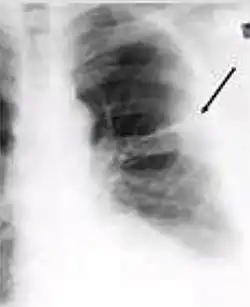

4. Pleural effusion - Presence of a significant amount of fluid within the pleural space. This finding must be distinguished from blunting of the costophrenic angle, which may or may not represent a small amount of fluid within the pleural space (except in children when even minor blunting must be considered a finding that can suggest active TB).

-

Chest x-ray showing dense opacity pleural effusion in the lower left lung of primary pulmonary TB.